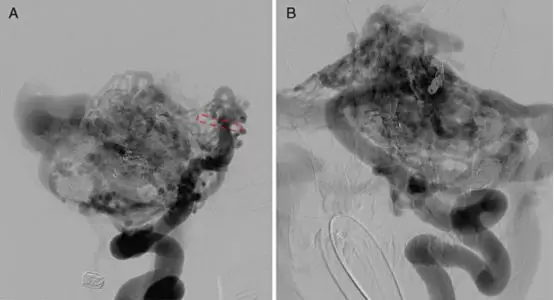

A,左侧颈总动脉造影,正位,显示左侧颈内动脉起始段闭塞,可见圆孔动脉(箭头)。B,圆孔动脉增粗,走行迂曲,与颈内动脉海绵窦段下外侧干吻合建立侧支循环。